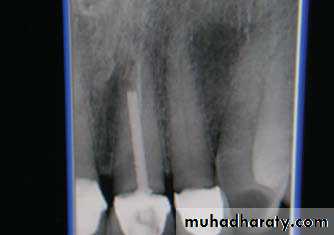

4- -Impacted teeth ,resorption of roots of adjacent teeth.